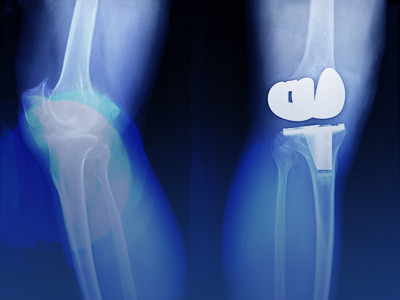

- Knee replacement (total and partial)

Joint replacement surgery involves removing the damaged surfaces of a joint and replacing them with durable artificial components designed to mimic the movement of a natural joint. This procedure can significantly reduce pain and increase range of motion, making everyday tasks easier and more enjoyable.